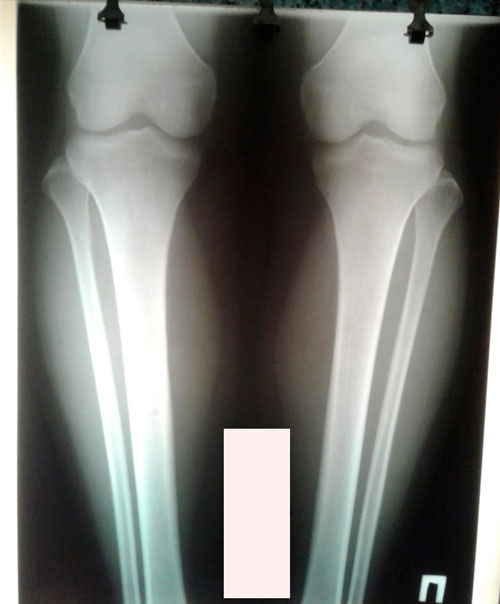

Исходник - 33 года. Киргизия.

Дата операции - 04.03.2019г.

рентген перед снятием аппаратов.